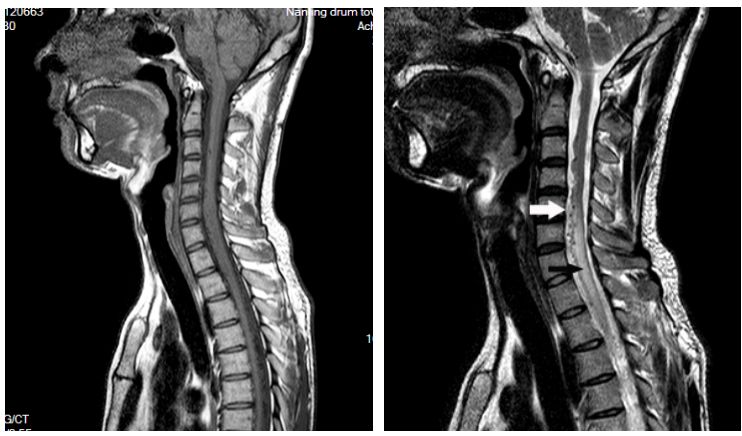

患者于2017年9月无明显诱因下出现右下肢无力,症状逐渐加重,在当地医院行膝关节核磁共振检查未见明显异常,3个月后至南京大学医学院附属鼓楼医院神经内科就诊,给予营养神经等对症治疗,并完善相关检查,肌电图示双下肢部分神经源性损害,双上肢未见明显异常;脊髓MR(本院,2017-12-16)示C5-T2层面脊髓明显增粗伴信号异常,颈髓及上段胸髓周围多发迂曲增粗血管影,考虑血管畸形伴脊髓脱髓鞘改变可能(图1)。入院查体:T36.4℃,P76次/分,R18次/分,BP105/78mmHg。双上肢肌力5级,双下肢4级,四肢肌张力正常,生理反射存在,病理反射未引出。入院初步诊断:脊髓血管畸形。

图1. 颈髓MRI蛛网膜下腔血管流空影(白色箭头)与脊髓水肿(黑色箭头)